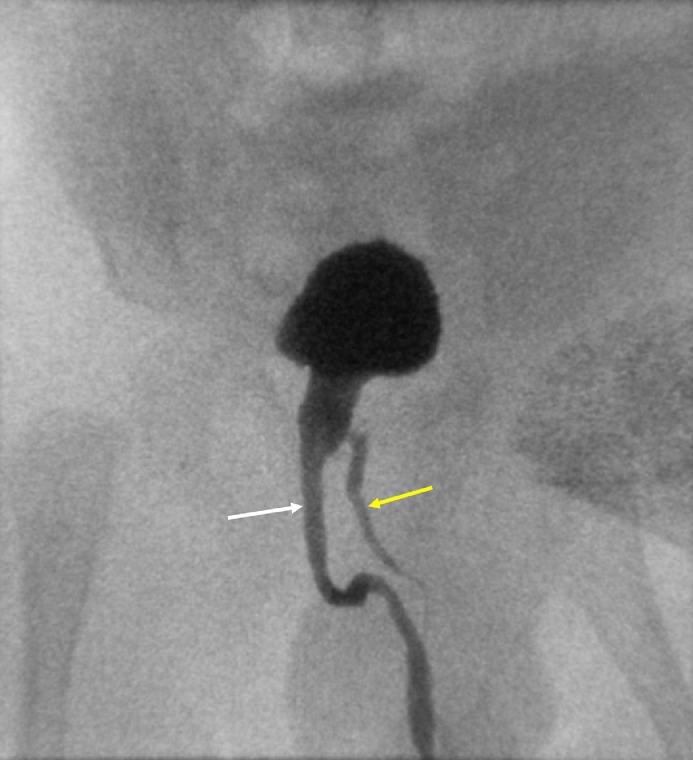

Diphallia or duplication of penis is extremely rare condition with a reported incidence of 1 in 5-6 million live births. Approximately around 100 cases of diphallia have been described in literature, each case have a unique presentation from associated anomalies. Clinically these patients can be classified into complete (true diphallia) or partial duplication. In true diphallia, each penis has 2 corpora cavernosa and 1 corpus spongiosum. If the duplicate penis is smaller or rudimentary with complete structure, it is described as true partial diphallia. The term bifid phallus is used if there is only one corpus cavernosum in each penis. Due to low incidence and varied presentation, not much is known about the underlying pathophysiology, management options, and outcomes. Here, we report a case of partial diphallia with associated penoscrotal transposition of 2 hemi-scrotums.

True partial diphallia with associated penoscrotal transposition of two hemi-scrotums.